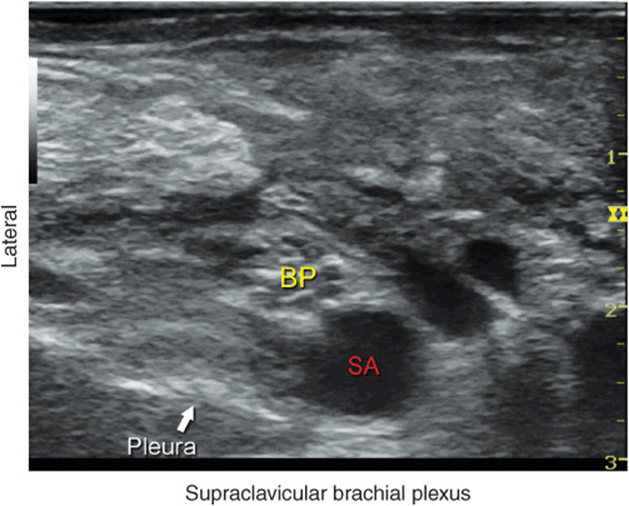

• When the visualization of the brachial plexus between the scalene muscles proves difficult, the transducer is lowered to the supraclavicular fossa. At this position, the brachial plexus is identified lateral and superficial to the subclavian artery, (Figure 29-6). From here, the brachial plexus is traced cranially to the desired level.

FIGURE 29-6. View of the brachial plexus (BP) at the supraclavicular fossa. When identification of the brachial plexus at the interscalene level proves difficult, the transducer is positioned at the supraclavicular fossa to identify the BP superficial and lateral to the subclavian artery (SA). The transducer is then slowly moved cephalad while continuously visualizing the brachial plexus until the desired level is reached.